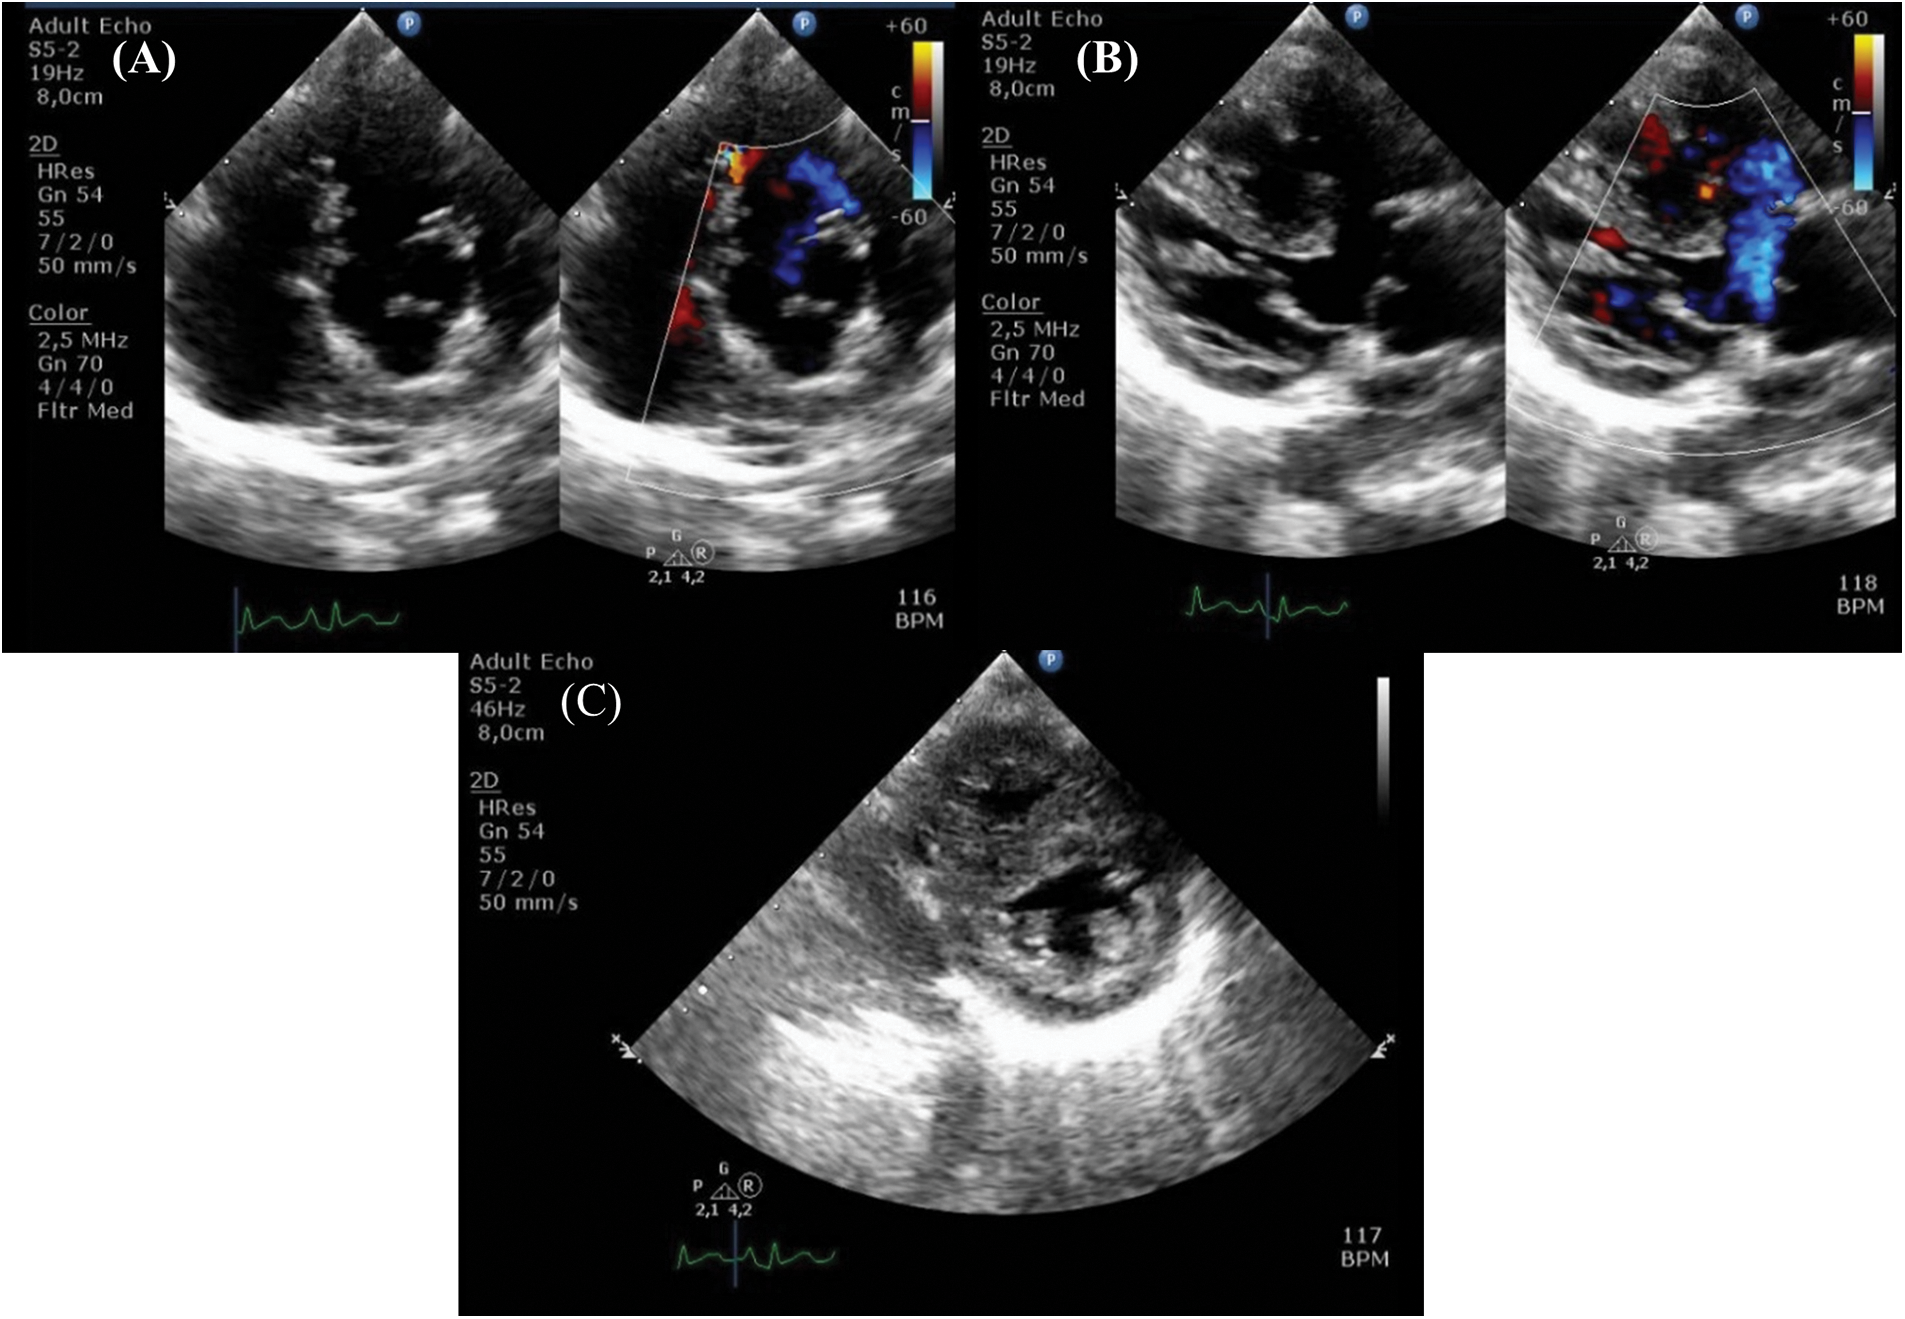

Her clinical characteristics, chest radiograph, and bedside transthoracic echocardiography (Figs. 2A–2C) supported the diagnosis of tetralogy of Fallot (TOF). Additional lesions were also identified, consisting of mixed-type TAPVC with the end of the pulmonary veins connected to the superior vena cava (SVC) and right atrial junction, and a large secundum atrial septal defect (ASD) (Figs. 3A and 3B). The preoperative pressure gradient across the right ventricular outflow tract (RVOT) was 58 mmHg. LA chamber was 17 mm in diameter (z-score < −3 for BSA 0.489 m2), and LV chamber during diastole was 21 mm (z-score < −3 for BSA 0.489 m2) [4]. Additionally, a multi-slice CT scan confirmed the diagnosis of TOF with mixed TAPVC (Fig. 4). The McGoon ratio of this patient was 1.802, which was deemed acceptable for TOF repair. No diagnostic challenges were identified. The patient was then scheduled for total corrective repair for the TAPVC, right ventricular outflow tract and chamber defects reconstruction in TOF, and creation of patent foramen ovale.

Figure 2: Preoperative echocardiography shows characteristics of tetralogy of Fallot (A) pulmonary stenosis, (B) overriding of the aorta, and (C) right ventricular hypertrophy

Figure 3: Preoperative echocardiography demonstrates (A) total anomalous pulmonary valve connection with (B) atrial septal defect